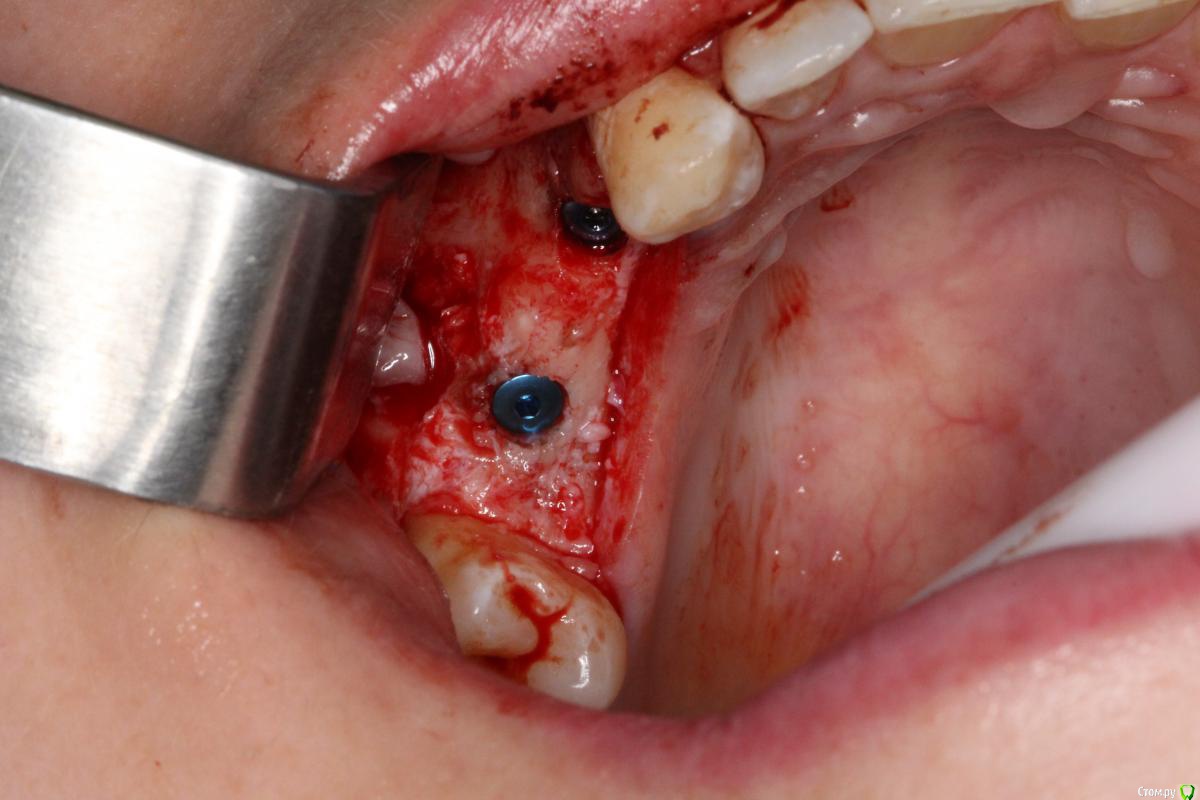

Robinbobin Опубликовано 25 марта, 2015 Поделиться Опубликовано 25 марта, 2015 Имплантаты Dio UF ll,костный материал ауто+остеоматрикс.Хотелось бы услышать мои ошибки 6 Ссылка на комментарий

red_butler Опубликовано 25 марта, 2015 Поделиться Опубликовано 25 марта, 2015 Robinbobin а зачем 1.4 так заглубили? Я бы плюсом сделал НКР на оба винта Ссылка на комментарий

Robinbobin Опубликовано 25 марта, 2015 Автор Поделиться Опубликовано 25 марта, 2015 Robinbobin а зачем 1.4 так заглубили? Я бы плюсом сделал НКР на оба винта Читал что шурупы конусные нужно заглублять,а нкр зачем?дефицита кости с вестибулярной стороны нету же вроде 1 Ссылка на комментарий

колесников Опубликовано 25 марта, 2015 Поделиться Опубликовано 25 марта, 2015 Вестибулярная компактная пластинка резорбируется на 3 мм у шеек имплантов. Вы конечно оставили дополнительно остеоматрикс вестибулярно ? В области 14 обязательно подсадите стт, можно на этапе формирователя. 16 можно было и короче взять,тогда бы он целиком находился в материале. А в целом Всё достойно. Ссылка на комментарий